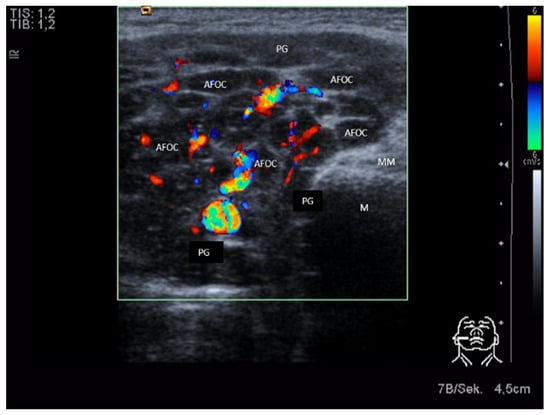

3.3.1. Acute or Subacute Primary Non-Obstructive Microbial Sialadenitis